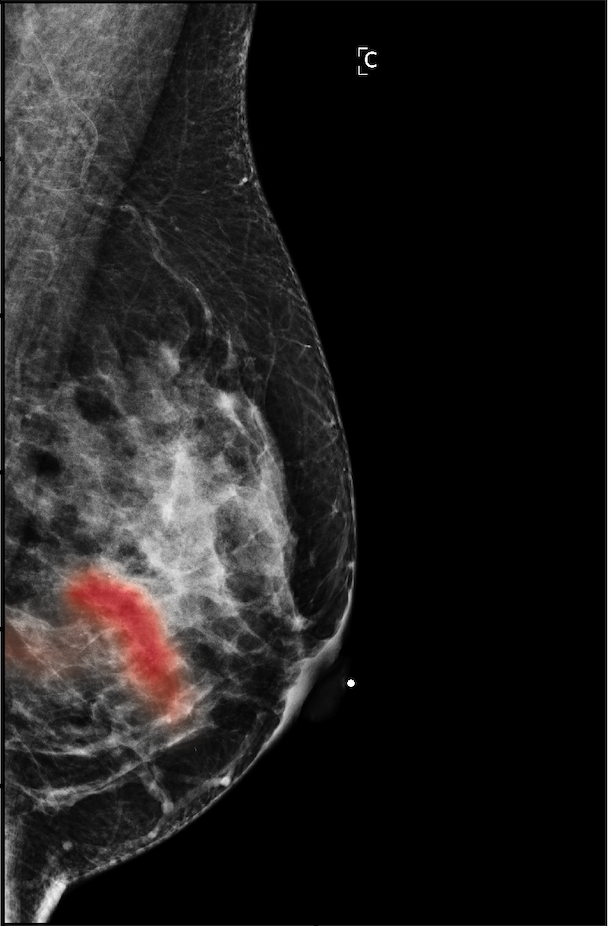

In Figure 7, we visualize saliency maps for four samples selected from the test set. In the first two examples, the saliency maps are highly activated on the annotated lesions, suggesting that our model is able to detect suspicious lesions without pixel-level supervision. Moreover, the attention is highly concentrated on ROI patches that overlap with the annotated lesions. In the third example, the saliency map for benign findings identifies three abnormalities. Although only the top abnormality was escalated for biopsy and hence annotated by radiologists, the radiologist’s report confirms that the two non-biopsied findings have a high probability of benignity and a low probability of malignancy. In the fourth example, we illustrate a case when there is some level of disagreement between our model and the annotation in the dataset. The malignancy saliency map only highlights part of a large malignant lesion with segmental coarse heterogeneous calcifications. This behavior is related to the design of : a fixed pooling threshold cannot be optimal for all sizes of ROI. The impact of is further studied in 3.6. This example also illustrates that while human experts are asked to annotate the entire lesion, CNNs tend to emphasize only the most informative regions. While no benign lesion is present, the benign saliency map still highlights regions similar to that in the malignancy saliency map, but with a lower probability than the malignancy saliency map. In fact, calcifications with this morphology and distribution can also result from benign pathophysiology [42].